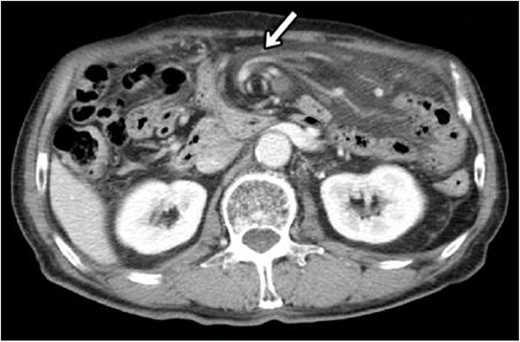

Laparoscopic surgery was initiated. Initial laparoscopic examination revealed an edematous small intestine with mild congestion and milky ascites (Fig. 2). The triglyceride level in the ascitic fluid was 670 mg/dL. Although we attempted to release the torsion laparoscopically, it was difficult to manipulate with forceps because of the edematous intestinal tract and mesentery; therefore, the patient was transferred to laparotomy. The entire small bowel was observed to be twisted 360° counterclockwise, and was therefore manually untwisted (Fig. 3). The duodenum was not fixed to the retroperitoneum as a horizontal leg, but was free from the retroperitoneum on the right side of the vertebral body. We examined the intestinal tract after untwisting and found no evidence of ischemia or necrosis. However, because a small palm-sized diverticulum was observed on the mesenteric side of the upper jejunum, partial resection of the small bowel, including the diverticulum area, was performed, considering the influence of secondary SBV (Fig. 4). The patient had a good postoperative course, but developed angina during hospitalization and was transferred to the cardiology department on postoperative Day 23.

Intraoperative photograph showing that the entire small bowel was twisted 360° counterclockwise.